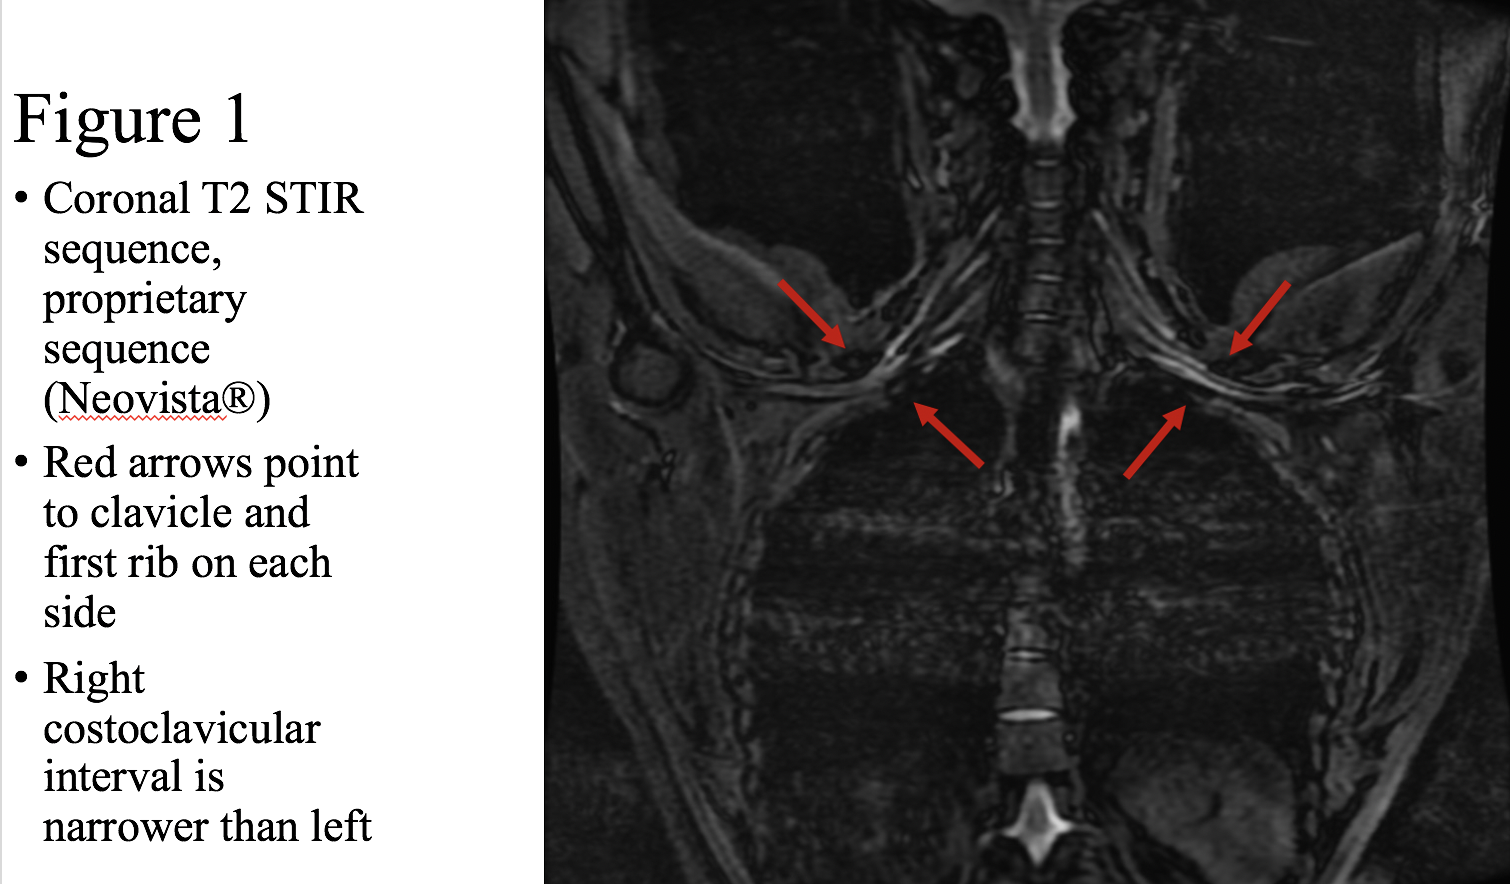

We present a patient with headaches, bilateral arm pain, and bilateral weakness. She has a positive EAST test bilaterally at 30 seconds. Right arm pain is worse with arms up, and this pain is reproduced by compression of the right costo-clavicular ligament. Left arm pain is worse with arms up, with weaker grip on Grip-X testing in the arm-up position, with reproduction of left radiating arm pain on compression of the left scalene muscles. Imaging demonstrates a narrowed costoclavicular interval on the right (1.0 cm, less narrowed on the left) with the arms abducted but no compression when the arms are down (Figure 1, Figure 2). This patient has two different types of TOS, both NTOS and ATOS, and because her story doesn’t fall classically into what we call “Occam’s Razor”, she was given the diagnosis of fibromyalgia by her neurologist.

Figure 1: NeoVista imaging showing Coronal T2 STIR sequence.